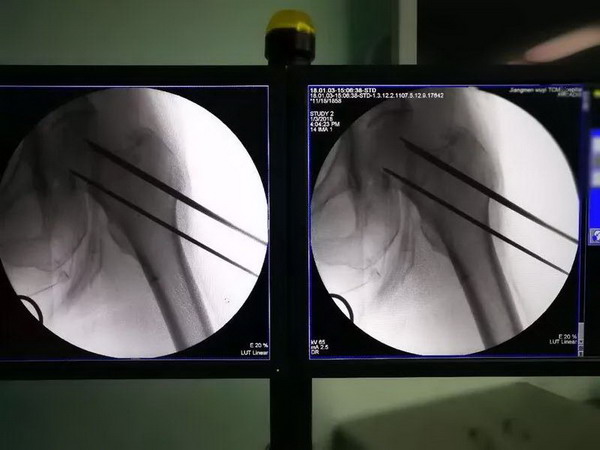

蓝阿姨摔了一跤后,她的右侧股骨颈出现骨折,在江门市五邑中医院治疗。经过会诊,医院医疗团队决定为蓝阿姨实施闭合复位空心螺钉内固定术,不过与以往不同的是,这次使用机器人辅助实施手术。

传统骨科手术是专科医生通过X光射线透视“看到骨头”进行定位,这种定位方式缺少立体空间,仅凭借“一双肉眼”难免出现“分厘偏差”,手术操作困难,且风险较高。

现在使用“天玑”骨科手术机器人,术中先利用C臂X光机对手术部位进行拍摄标记,然后将图像传送到计算机上,并进行置钉位置规划,然后利用导航技术,类似GPS一样,引导机械臂到指定位置。这样,医生就可以在机器人的辅助下准确置入内固定,可精确到0.8mm以内,真正实现“毫厘不差”,让手术更完美。

在骨科机器人的协助下,这台手术时间短,手术创伤很小,手术切口约1厘米,而且没有什么出血。简单来说,就是精准、微创、耗时少。这是我市首例机器人辅助骨折固定术,也标志着我市骨科手术正式迈入了智能化、精准化、微创化的机器人手术新时代。

“机器人的成功应用,使我们的手术操作简单了。机器人规划精准路径,把手术难点解决了。我们只要把螺钉打进去就可以,由于精准度更高,大大降低了医疗风险,患者更有安全感。”区文欢主任说。

目前,江门市五邑中医院在机器人应用方面主要应用在股骨颈骨折空心钉内固定、骨盆骨折空心钉内固定以及脊柱椎弓根置钉等。就拿股骨颈骨折来说,准确的置钉可以使到股骨颈骨折端均匀加压,骨折端更稳定,有利于骨折的愈合和减少股骨头坏死的风险。